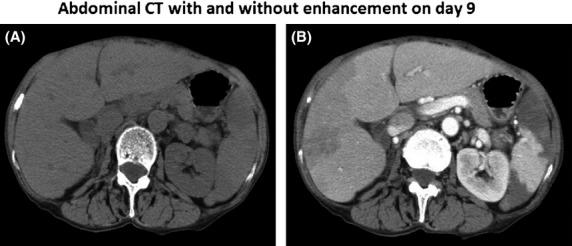

It is well-known that the major organisms for mycotic aneurysms are Staphylococcus aureus, Salmonella spp but is extremely rare in Streptococcus pneumoniae in postantibiotic era. We demonstrated the first case with multiple mycotic aneurysms simultaneously generated in the splenic and hepatic arteries in a patient with pneumococcal pneumonia.

众所周知,霉菌性动脉瘤的主要病原体是金黄色葡萄球菌、沙门氏菌属,但在抗生素时代后,肺炎链球菌引起的霉菌性动脉瘤极为罕见。我们报道了首例在肺炎球菌肺炎患者的脾动脉和肝动脉同时发生多发性霉菌性动脉瘤的病例。